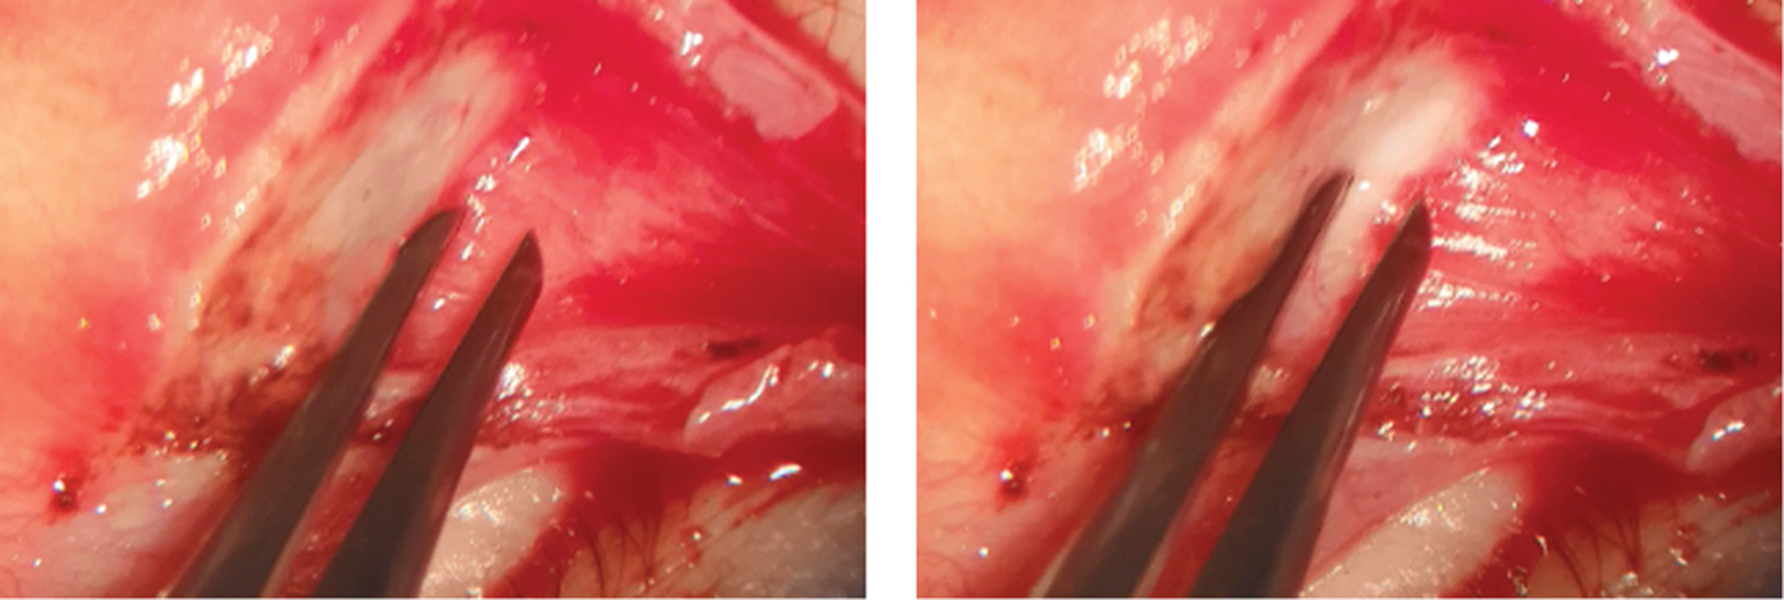

The white line mobility varied significantly from 0 to 4 mm in our cases (Fig. 3, 4).

Fig. 4. Example of 1 mm white line motility

Рис. 4. Пример подвижности белой линии 1 мм